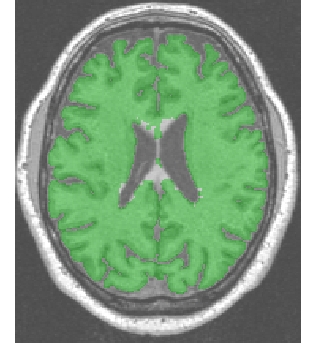

Eroded cerebral structures

Some of the gyri have been lost somewhere:

This problem occurs with very thin gyri, which width is less than two times the erosion size. Try the variants beginning with a 1.5mm erosion size:

"Standard/Robust (iterative or fixed erosion from 1.5mm)"